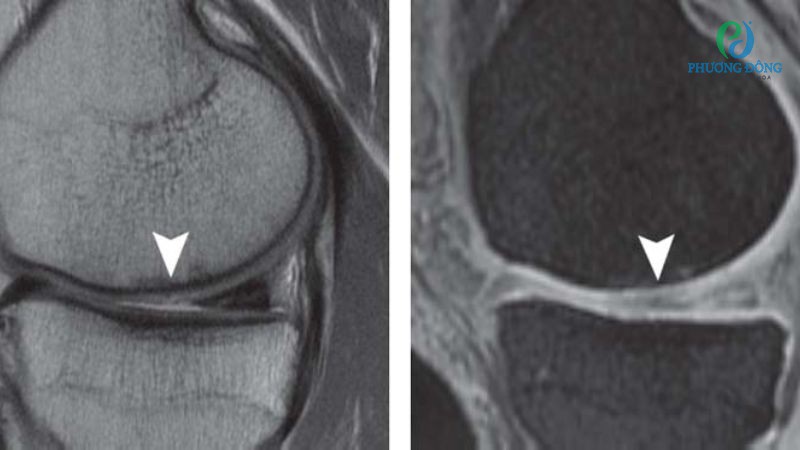

Phương pháp chẩn đoán

Để xây dựng phác đồ điều trị dứt điểm, bác sĩ cần tiến hành khai thác triệu chứng của người bệnh kết hợp với các xét nghiệm cận lâm sàng. Bao gồm:

- Chụp X-quang khớp giúp truy vết, đánh giá tình trạng lắng đọng tinh thể canxi trong khớp.

- Chọc dịch khớp trong trường hợp cần xác định nguyên nhân có liên quan đến tinh thể canxi pyrophotphat hay không.

Tùy từng trường hợp bác sĩ sẽ có chỉ định khai thác bệnh lý cụ thể, đảm bảo phân biệt chính xác với các bệnh lý xương khớp khác. Dựa vào đó cung cấp phác đồ điều trị phù hợp, an toàn cho người bệnh.